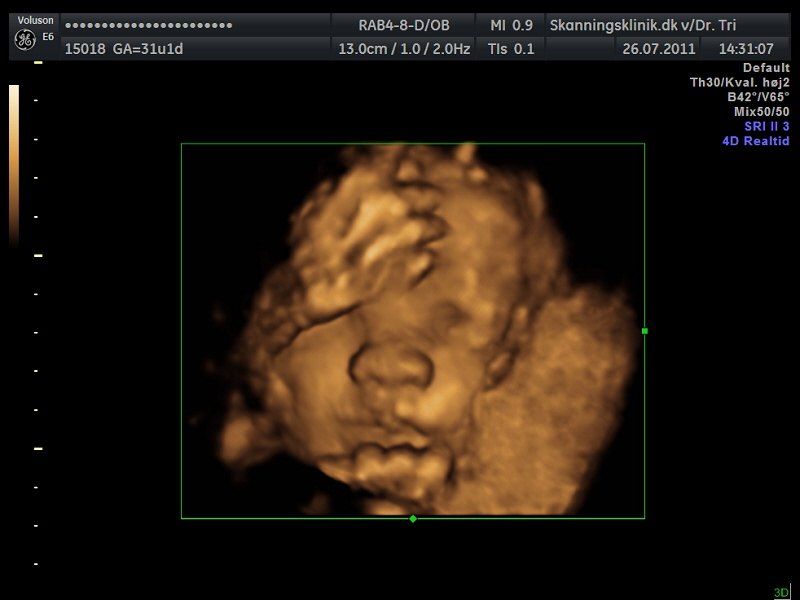

Så blev det tid til en lille 3D/4D-scanning af bettemanden!!

Jeg er i dag 31+2 og var i eftermiddags til 3D/4D-scanning, på skanningsklinikken i Hvidovre, og sikke en oplevelse, helt sikkert alle pengene værd!!

Lillemanden var dog noget svær at få gode billeder af, da han havde skruet numsen ned i mit bækken og synes han skulle ligge med begge hænder og fødder direkte foran hans lille nuttede ansigt hehe.. Så mor her måtte op at hoppe flere gange og fik koldt vand og måtte have maven gennem-rystet flere gange, men alligevel var han nooget på tværs hehe.. Den lille bølle..

Men der kom dog til sidst nogle helt okay billeder ud af det!!

Og så liige lidt billeder, så I også kan se min fine guldklump...

Som I kan se er der lidt hånd og fod med på alle billederne, og på det sidste billede har bettemanden fat om foden med den ene hånd.. Lille hypermobile skid..